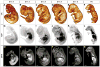

Background: Microcomputed tomography (micro-CT) has been used extensively in research to generate high-resolution 3D images of calcified tissues in small animals nondestructively. It has been especially useful for the characterization of skeletal mutations but limited in its utility for the analysis of soft tissue such as the cardiovascular system. Visualization of the cardiovascular system has been largely restricted to structures that can be filled with radiopaque intravascular contrast agents in adult animals. Recent ex vivo studies using osmium tetroxide, iodinated contrast agents, inorganic iodine, and phosphotungstic acid have demonstrated the ability to stain soft tissues differentially, allowing for high intertissue contrast in micro-CT images. In the present study, we demonstrate the application of this technology for visualization of cardiovascular structures in developing mouse embryos using Lugol solution (aqueous potassium iodide plus iodine).

Methods and results: We show the optimization of this method to obtain ex vivo micro-CT images of embryonic and neonatal mice with excellent soft-tissue contrast. We demonstrate the utility of this method to visualize key structures during cardiovascular development at various stages of embryogenesis. Our method benefits from the ease of sample preparation, low toxicity, and low cost. Furthermore, we show how multiple cardiac defects can be demonstrated by micro-CT in a single specimen with a known genetic lesion. Indeed, a previously undescribed cardiac venous abnormality is revealed in a PlexinD1 mutant mouse.

Conclusions: Micro-CT of iodine-stained tissue is a valuable technique for the characterization of cardiovascular development and defects in mouse models of congenital heart disease.